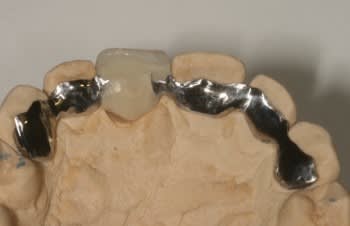

fig 1 coupe tomo Jo

fig 2 vue clinique ( léger décalage des collets entre 11 et 21 )

fig 3 exo

fig 4 pose membrane résorbable + os xénogène

fig 5 membrane suturée

fig 6 réouverture J0 + 6mois

fig 7 vue clinique J0 + 2ans ( Prothèse Dr G.D 31 )

fig 8 vue clinique JO + 5ans (léger décalage des collets entre 11 et 21 comme à l'origine)

fig 9 radio J0 + 5 ans

Son praticien lui avait réalisé en amont un bridge collé.

je lui ai posé le jour de la première chirurgie